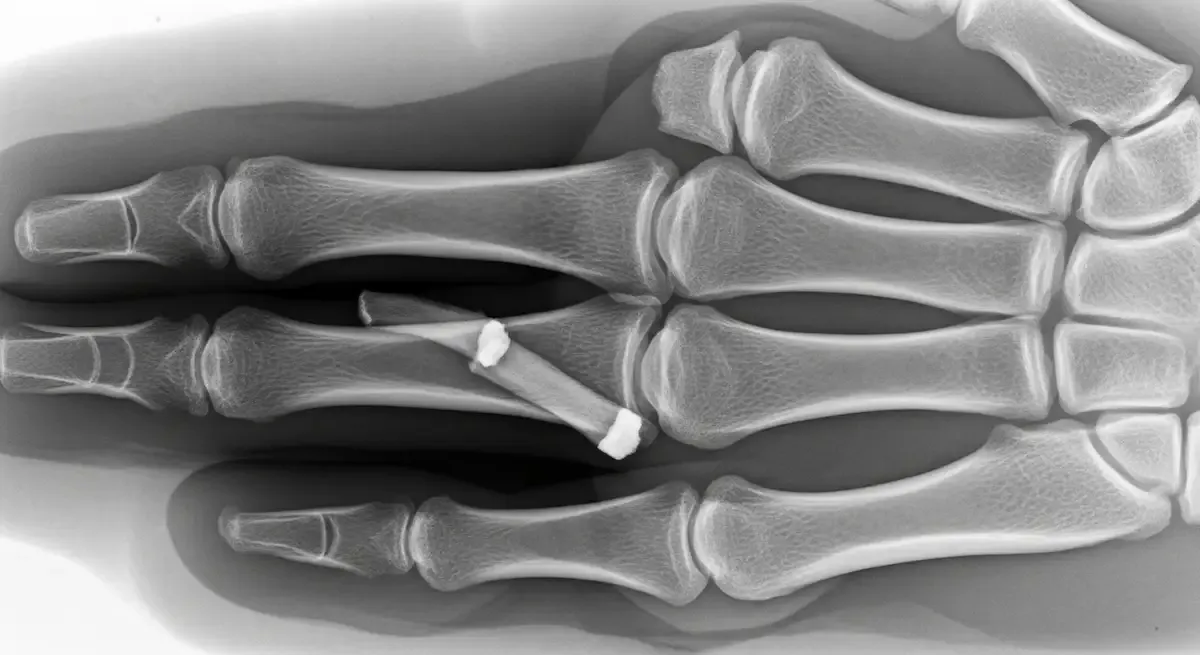

• Radiografias do dedo afetado em três projeções ajudam a identificar fratura por avulsão e descartar luxações.

Torções laterais podem agravar a lesão e comprometer os ligamentos colaterais. Em parte dos casos, ocorre fratura por avulsão, quando um pequeno fragmento ósseo se solta no ponto de inserção da placa.